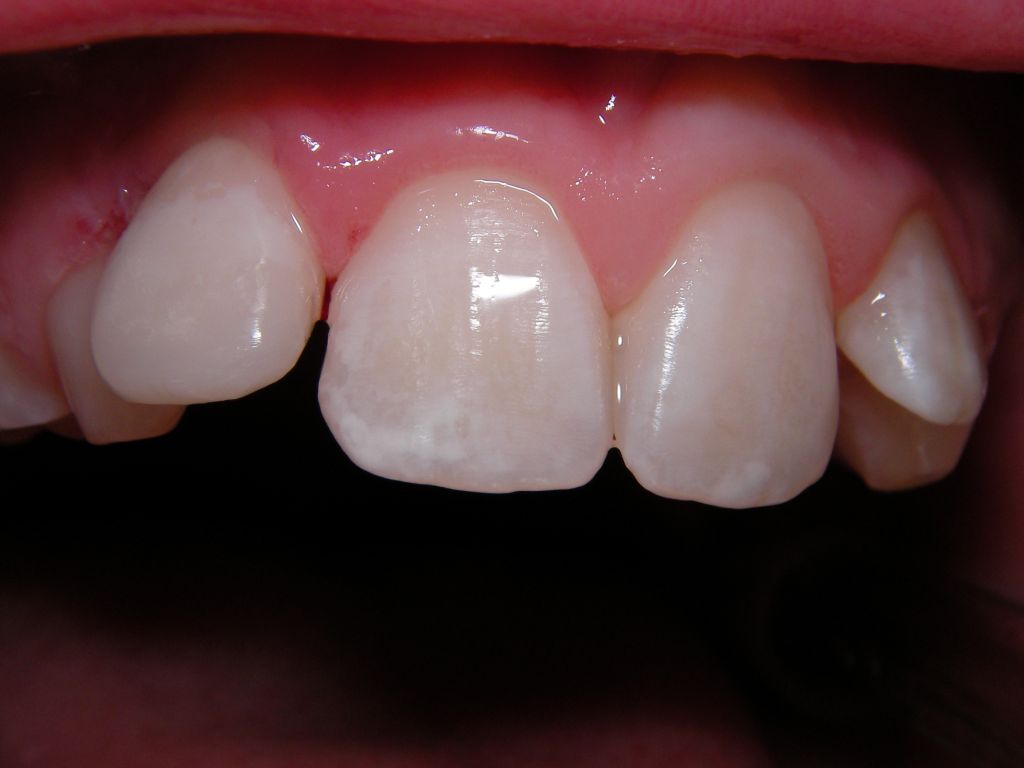

На фотографии зубы,пораженные кариесом начального этапа – белый кариес, когда на зубной эмали видны матовые белые пятна.

Первоначальным этапом кариеса на стадии пятна принято считать состояние белого кариеса. Заболевание отличается появлением матовых белых пятен по всей поверхности зубной эмали. Врач может наблюдать формирование массивных отложений и легкого зубного налета. Это свидетельствует о проведении неполноценных гигиенических процедур в ротовой полости пациента.